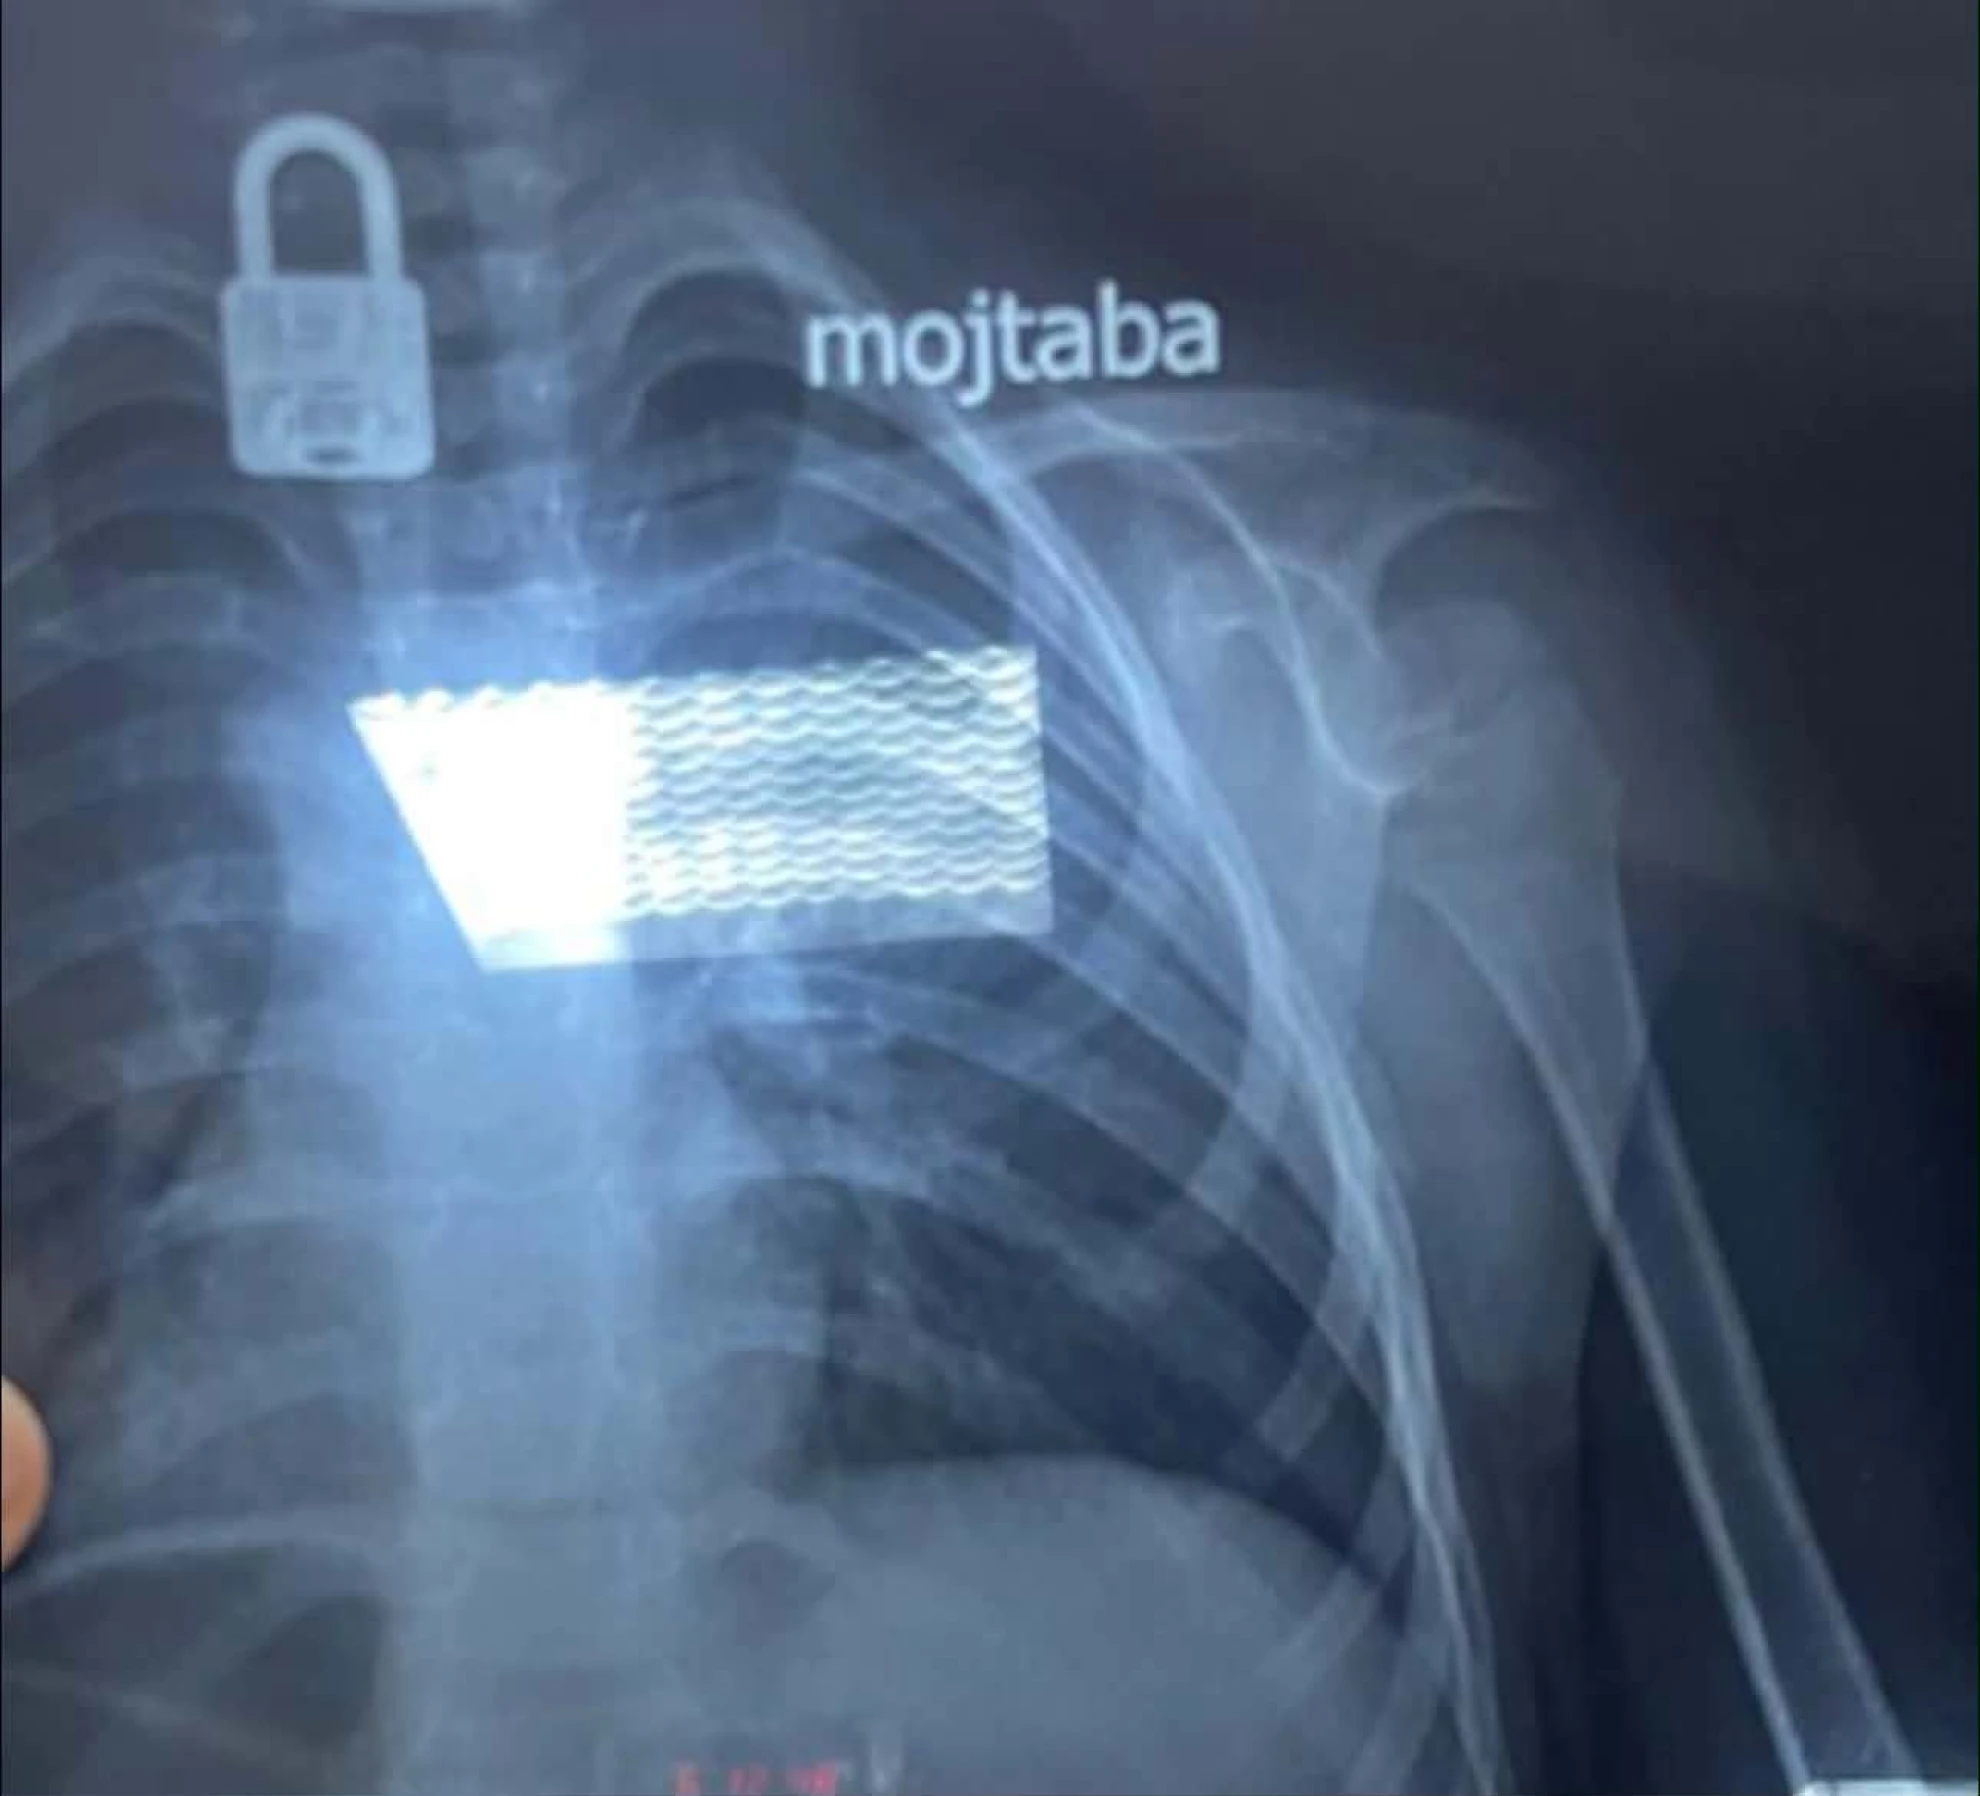

حبوب المخدرات المضبوطة والقفل داخل جسم الطفل بفحص الأشعة

حبوب المخدرات المضبوطة والقفل داخل جسم الطفل بفحص الأشعة

أما في النجف، فقد ذكرت دائرة صحة المحافظة في بيان ورد لوكالة شفق نيوز، أن مستشفى الزهراء التعليمي/ قسم جراحة الأطفال استقبل حالة طارئة لطفل يبلغ من العمر أربع سنوات قام بابتلاع جسم غريب.

وبعد إجراء فحص بالأشعة السينية للطفل تبين وجود "قفل" داخل جسمه، وعلى إثر ذلك، بحسب دائرة الصحة، تم التنسيق مع مدينة الصدر الطبية / قسم جراحة القلب والأوعية الدموية لاستخراج "القفل"، وتم ذلك بنجاح عن طريق الناظور، والطفل الآن بحالة صحية جيدة.